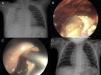

(A) Chest radiography demonstrating a cavity with air–fluid level in its interior in the right hemithorax. (B) Pre-operative CT shows a lesion compatible with abscessed necrotizing pneumonia in the right lower lobe. (C) Intraoperative image of the lung abscess; note the greenish appearance of the parenchyma and the surrounding air bubbles caused by the BPF. (D) Radiological check-up 2 months after surgery.

(A) Pre-operative thoracic radiography with right empyema reaching the lung apex. (B) Thoracoscopic image showing the drainage of the content of the abscess. (C) Intraoperative image of the cavity of the abscess after the evacuation of the detritus. (D) Radiological check-up 2 months after surgery.